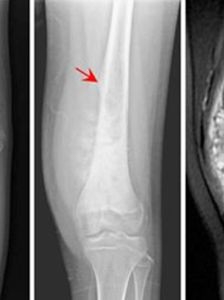

X線片表現

骨質緻密度不一。有不規則的破壞,表面模糊,界限不清,病變多起於骺端,因腫瘤生長及骨膜反應高起形成考德曼氏三角,有與骨幹垂直方向的放射形骨針。

骨肉瘤1、多發於15—25歲青少年,好發於四肢長管骨幹骺端。膝關節上下部位最常見。

6、X線攝片之特徵。